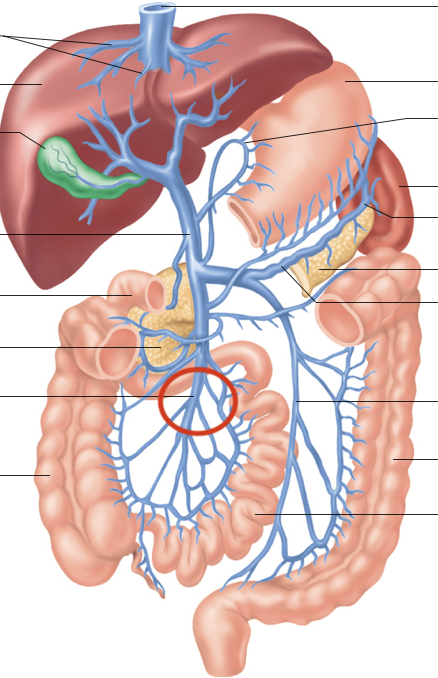

Hepatic Portal System (illustration)

hepatic portal vein

superior mesenteric-small intestine, first half colon

gastric-stomach

splenic-spleen and pancreas

inferior mesenteric-second half colon

hepatic veins